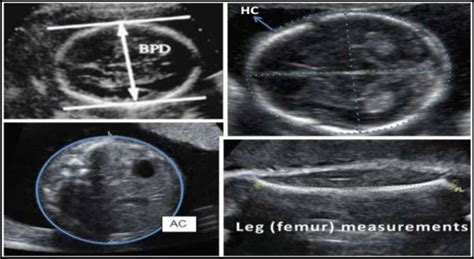

• BPD (Biparietal Diameter): This measures the diameter of your baby’s head from one side to the other. It’s like measuring the width of their head. The BPD is crucial because it helps doctors estimate the baby’s gestational age and size. During the 30th week, this measurement is particularly important as the brain is developing rapidly. Monitoring BPD helps to ensure the baby’s head size aligns with the expected growth curve, potentially indicating the need for further assessments if deviations are observed. BPD is a key indicator of fetal development, which also gives insights into how well the baby is thriving inside the womb. Deviations from the normal range could sometimes point to potential issues that require further investigation. So yeah, it’s a pretty important measurement!

• HC (Head Circumference): As the name suggests, this is a measurement of the circumference of your baby’s head. It’s like measuring around their head, like you would measure your own head for a hat. Along with BPD, HC is a crucial measurement for assessing the overall growth of the baby’s head and brain. Doctors use this to make sure the baby’s head is growing at a healthy rate. It provides a more comprehensive view of the head’s size compared to just the width (BPD). It is a vital measurement for helping to confirm your baby’s gestational age. Measuring HC also helps identify any potential issues with brain development. Both BPD and HC are super important for making sure everything is progressing smoothly. Monitoring HC is essential in identifying conditions such as microcephaly (small head) or macrocephaly (large head), which might affect the baby’s health. That is why it is so important!

• AC (Abdominal Circumference): This measures the circumference of your baby’s abdomen. This measurement is often used to estimate the baby’s weight and assess the growth of the baby’s abdomen. AC provides information about the baby’s overall size and nutrition. This helps in understanding the baby’s nutritional status and assessing any potential growth restrictions or overgrowth. This measurement is particularly useful in identifying issues related to the baby’s abdominal organs, like the liver. It’s important for assessing the baby’s overall health and well-being. Monitoring AC is also key in detecting conditions such as intrauterine growth restriction (IUGR) or macrosomia (large baby). When the baby’s abdomen size is not within the normal range, it could indicate potential problems that need further evaluation. It’s a great indicator of your baby’s well-being!

• FL (Femur Length): This measures the length of your baby’s femur, which is the thigh bone. This measurement helps in estimating the baby’s size and can also give insights into the baby’s skeletal development. FL is a great indicator of the baby’s overall growth and proportions. It’s useful for understanding the baby’s skeletal development and can also help assess the baby’s overall size and growth. FL is a reliable indicator of fetal growth and is frequently used to determine if the baby’s long bones are developing normally. Monitoring the FL also helps in determining the baby’s overall growth and in identifying any potential skeletal abnormalities. This helps ensure that the baby’s long bones are developing as they should. Pretty neat, huh?